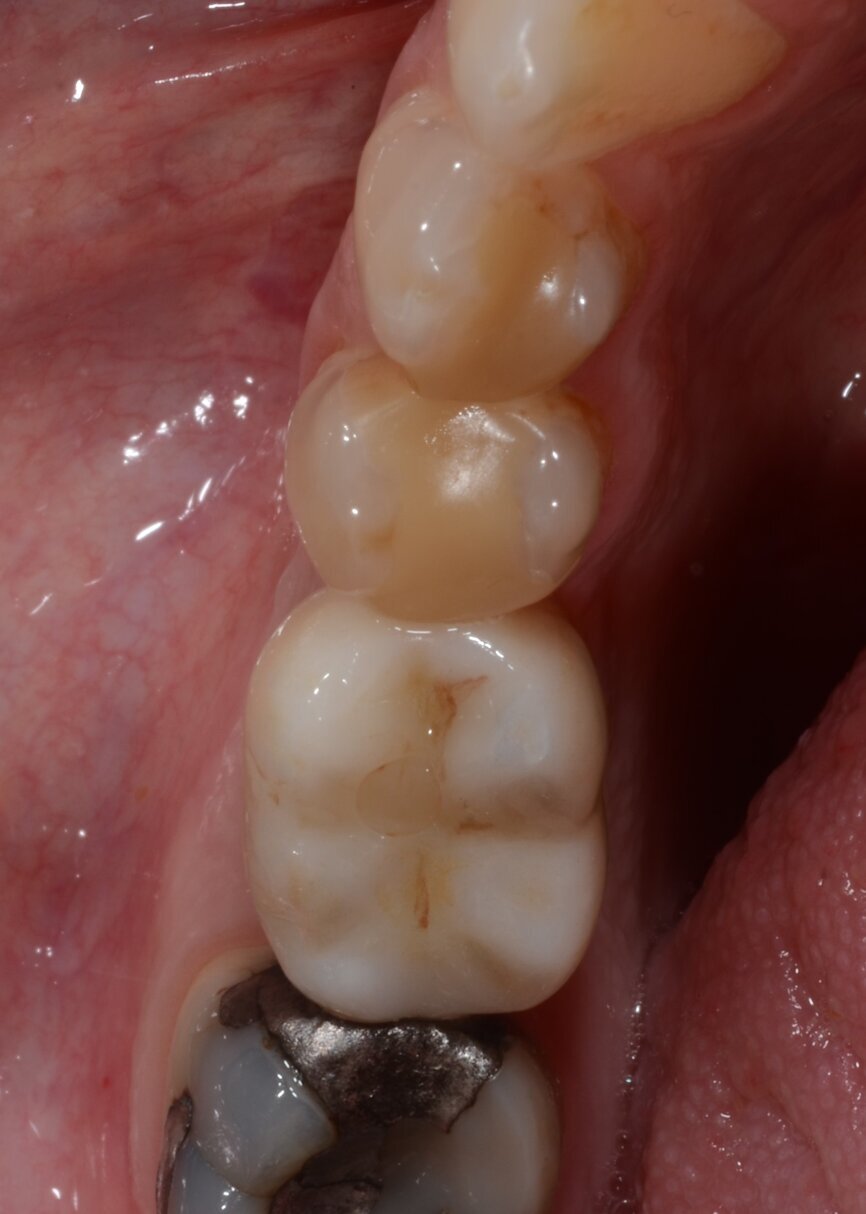

After 12 weeks, Salvesen removed the temporary crown, revealing that the soft tissue had healed very well (Fig. 15). He then began the digital workflow. For the final crown, a digital impression was taken with a 3Shape intra-oral scanner, using a Straumann CARES scan body. A monolithic zirconia crown was then seated passively on to the implant in a healed and preconditioned soft-tissue environment (Figs. 16–19).

Fig. 18: Final crown in position, lateral view.

Fig. 20: One-year follow-up occlusal view.

Fig. 21: One-year follow-up lateral view.